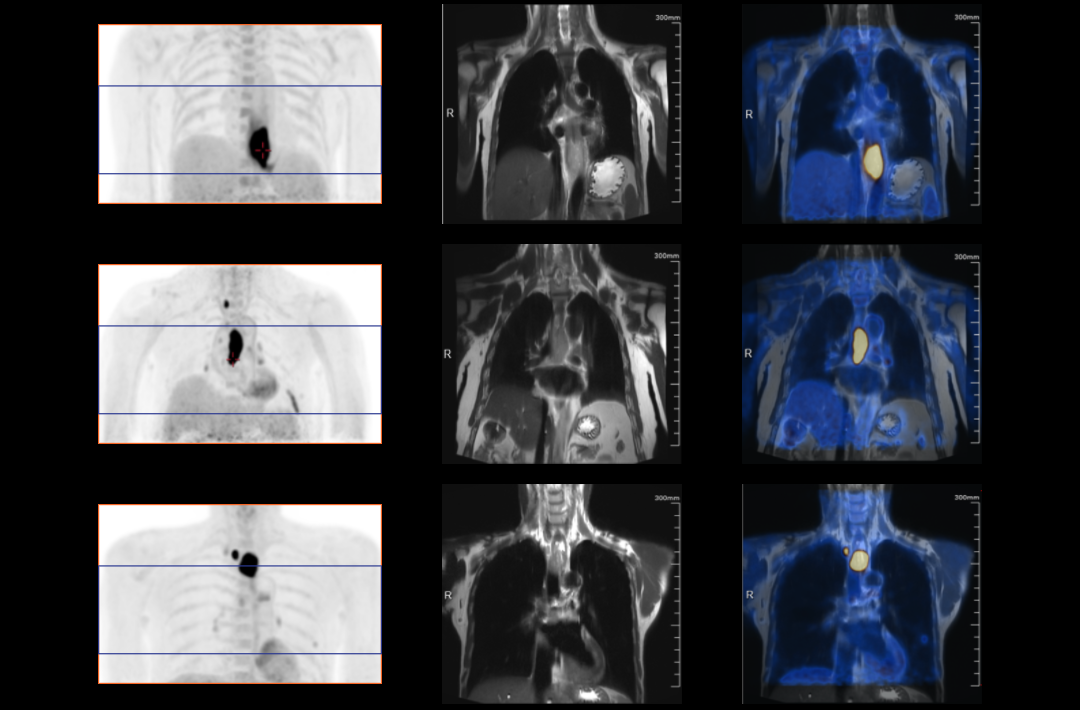

Compared with the conventional PET system with AFOV ranging between 20cm and 25cm, the 32cm long AFOV not only improves the sensitivity of the system, but also basically covers main organs of the whole body and the regional lymphatic system where metastasis may occur, and makes it possible to realize cancer TN staging in one bed position.

Traditionally, a PET/MR scan of a tumor patient takes about 35 to 50 minutes. The long AFOV can further optimize the PET/MR tumor scanning scheme. In other words, it can optimize the decision about whether to scan the whole body based on whether the tumor patient has regional lymphatic metastasis after regional PET/MR scan, potentially saving scan time for patients without metastasis.

In August 2019, Peking Cancer Hospital introduced United Imaging Healthcare's integrated PET/MR to make an in-depth exploration and optimization of cancer TNM staging under long AFOV. More than 500 examples of scanning various organs proved that long AFOV PET/MR could greatly increase the scan range over one bed position and improve the efficiency of cancer TNM staging.

The following are the cases of optimized TNM staging of breast cancer, esophageal cancer, prostate cancer and other diseases under the long axial field of "spatio-temporal integration" ULTRA-clear TOF PET/MR.  Thanks to Capital Medical University Xuanwu Medical Treatment for providing the image.